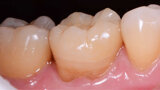

Fig. 1. Situación inicial.